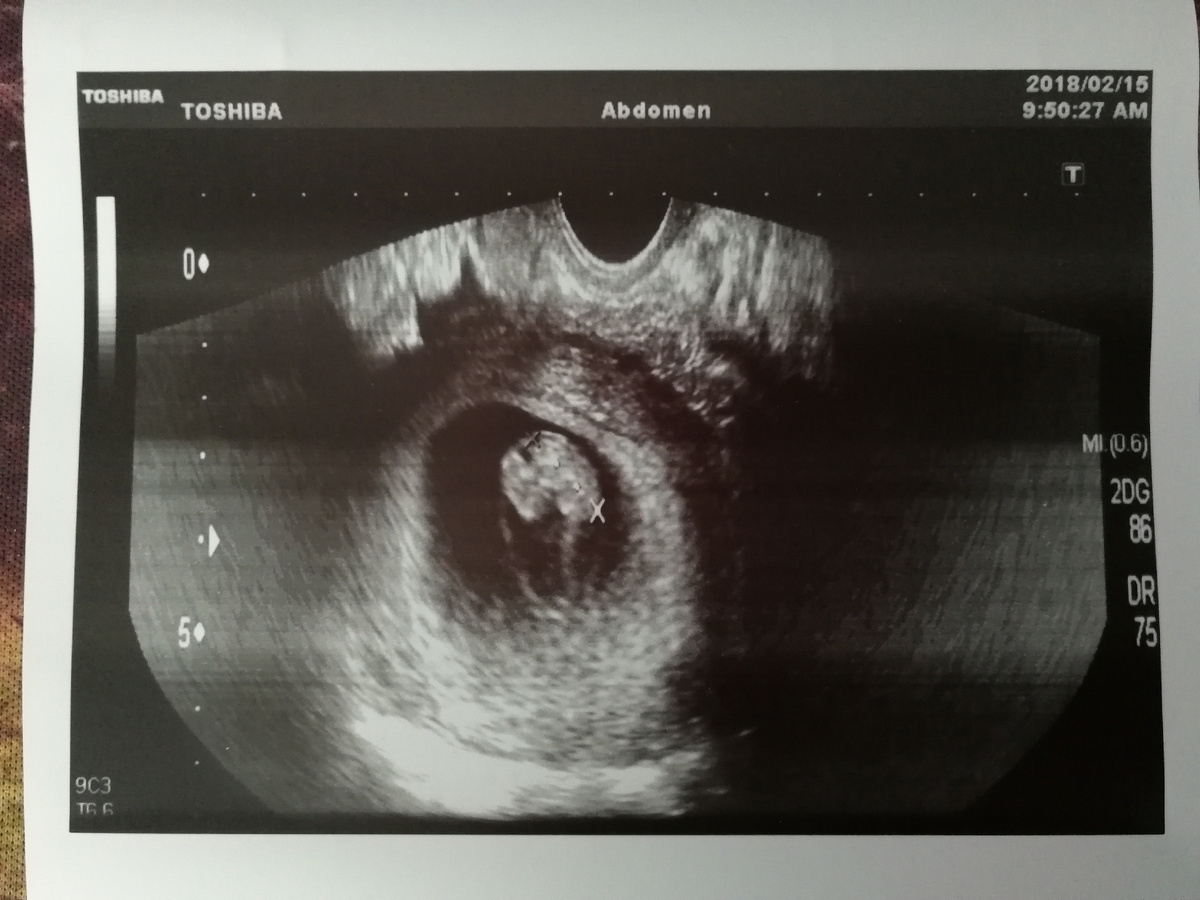

2. Первое УЗИ. Самое первое - самое запоминающееся. Ведь на нем можно увидеть своего малыша, пусть и на черно-белом экране, пусть и не совсем похожим на человека, а скорее - на креветку (если это на раннем сроке беременности). И если делать УЗИ в 7-8 недель беременности, то уже можно услышать, как бьется маленькое сердечко ребенка. Удивительно! Осознаешь, что внутри тебя начинается развиваться новая жизнь.

3. "Весточки от аиста". Когда хочется интересно сообщить о своем "положении" родным: будущим бабушкам и дедушкам, тетям и дядям, а также братьям и сестрам малыша, - стоит подключить творческий подход. Я решила нарисовать Аиста, который и принесет важное послание в виде небольших открыток нашим родственникам. Внутри открыточки я вклеила копию "фотографии" с нашего первого УЗИ. Напечатала текст от имени Малыша. А на открытке с помощью трафарета от руки написала "Для Вас пришла хорошая весточка". Получилось мило. А главное, всем понравилось и растрогало до слез)